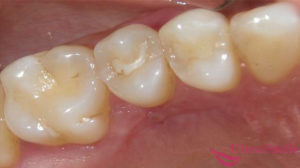

Проникновение в герметичную полость каналов с помощью медицинского инструмента

Обеспечив с помощью специальных боров доступ к очагу острого или хронического воспаления в просвете корневого канала зуба, врач стоматолог механически удаляет из просвета корня воспаленную пульпу зуба и всю нежизнеспособную костную ткань.

После завершения обработки канала зуба в просвет канала аккуратно закладывают специальное антибактериальное лечебное средство, которое полностью уничтожает инфекцию в зубе и обеспечивает полную дезинфекцию очага воспаления.